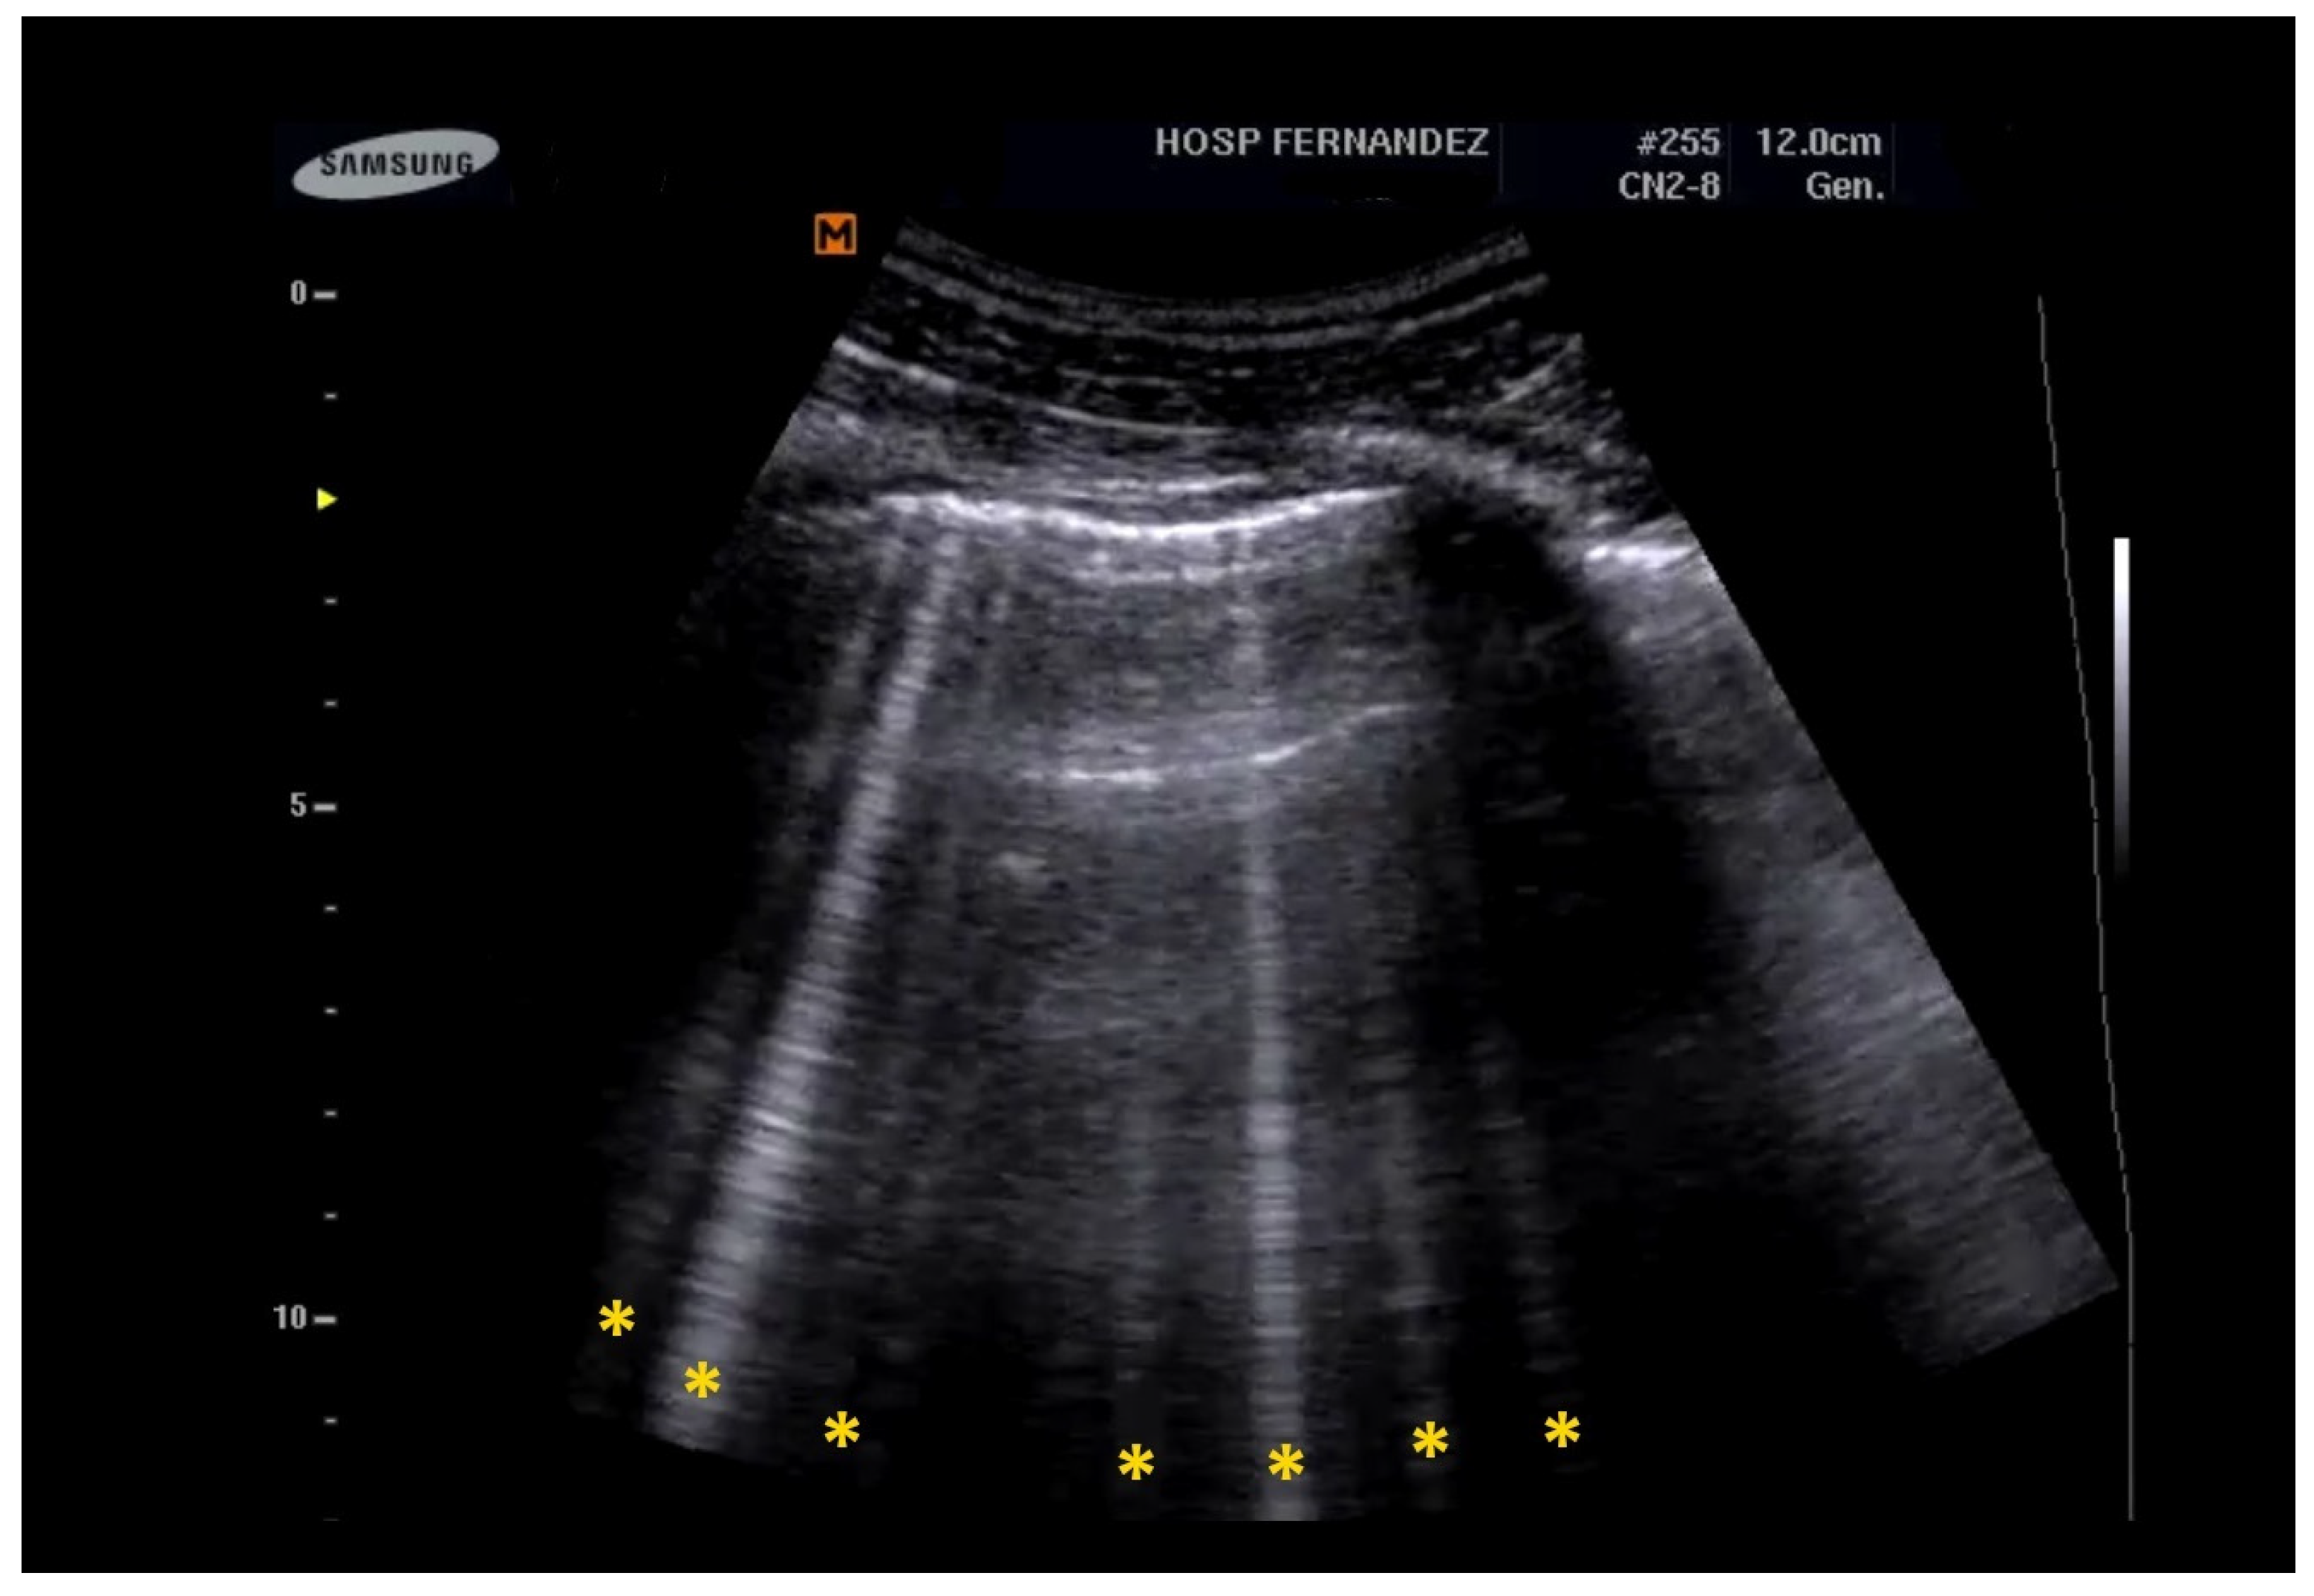

- Multiple B-Lines: These appear in a diffuse, inhomogeneous distribution and are critical for ILD diagnosis.

- Pleural Line Abnormalities: These may include thickening, irregularities, and fragmentation of the pleural line.